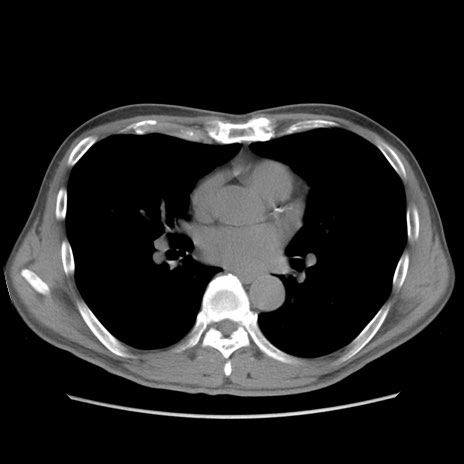

症例56 CT(横断像)

脂肪ウインドウ